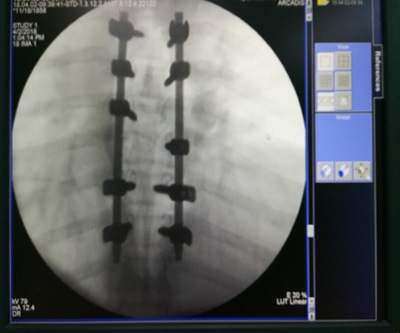

手术顺利为孕妇胸椎打钉

4月2日上午,医疗组为孕妇进行了“经后路胸椎骨折切开复位+椎管减压+植骨融合内固定+右锁骨骨折切开复位+内固定手术”,手术室选派郑敏主管护师、连剑娥护师协助手术护理。在全体手术人员的密切配合下,手术进展顺利,患者术后安全返回病房,目前正在进一步恢复中。